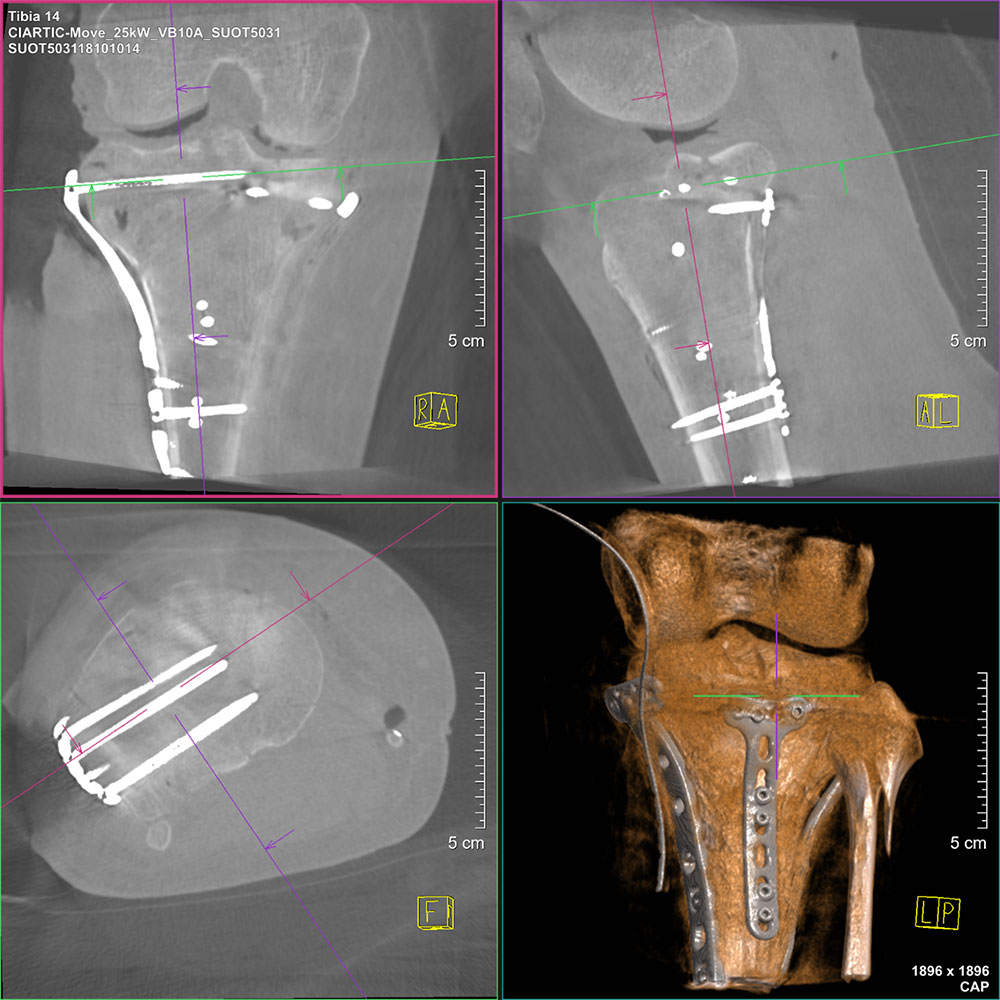

CIARTIC Move Mobile C arm with CBCT capabilities.

Intraoperative CBCT has been gaining some acceptance in orthopedic surgery via mobile C arms. Siemens Healthineers was the first to introduce CBCT in the ARCADIS Orbic 3D mobile C arm in 2004. In the current portfolio, it’s been replaced by the CIARTIC Move (Move) and the Cios Spin (Spin). The benefits associated with the use of intraoperative CBCT in orthopedic surgery are well documented.5,6

A study published in the Journal of Orthopedic Surgery and Research evaluated the revision rate of pedicle screw implantations in a patient with and without 3D intraoperative imaging.7 The researchers concluded that intraoperative CBCT is a reliable tool for assessing implant positioning and fracture reduction, potentially decreasing the necessity for postoperative revisions.

Research highlighted in EFORT Open Reviews discussed the advantages of intraoperative CBCT in orthopedic trauma surgery. The study emphasized that immediate control of fracture reduction and implant positioning through high- quality 3D imaging can reduce the need for secondary revision surgeries due to implant malposition.8

With high quality 3D imaging for diagnosis and surgical treatment, the Rax, Spin and the Move are poised to provide the patient with an accurate diagnosis and the surgeon with enhanced surgical accuracy. The overall average revision rate for orthopedic surgery was 19%.5 Higher revision rates are seen in the heal, tibia, ankle and foot (36%-20%), all weight-bearing regions. The 90-day episode cost for orthopedic revision surgery in 2019 was $48,987.9 In 2024, the cost for that same surgery increased to $55,413.09, when indexed for inflation.10 Significant benefits can be obtained in both the diagnostic and intraoperative orthopedic environments by using CBCT imaging.

Image of a CBCT done on the Move showing the coronal, sagittal and axial planes and 3D reconstruction of a tibia fracture.